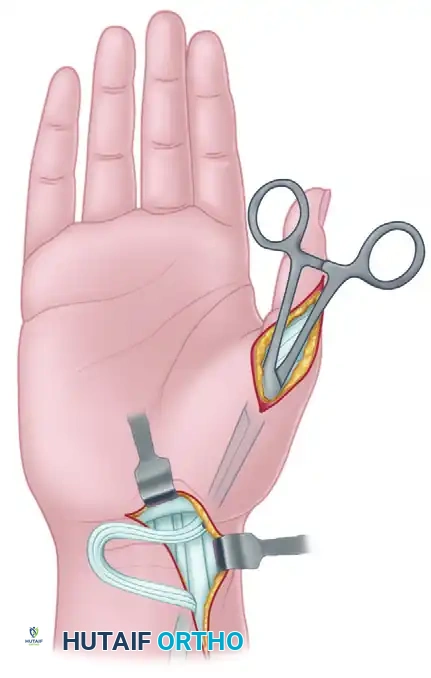

3. Proximal Tendon Harvest

- Incision: Make a longitudinal incision in the volar forearm, positioned just radial to the tendon of the flexor carpi radialis (FCR). Curve the distal portion of this incision ulnarward to avoid crossing the wrist flexion creases at a perpendicular angle.

- Dissection: Incise the antebrachial fascia. Retract the FCR ulnarward and the radial artery radially.

- Identification: Identify the FPL tendon at its musculotendinous junction. Apply distal traction to the transected tendon in the thumb to confirm its identity in the forearm.

- Withdrawal: Carefully draw the FPL tendon out of the carpal tunnel and into the forearm incision. Ensure there are no adhesions or vincula tethering the tendon distally.

4. Subcutaneous Tunneling and Rerouting

- Create a generous subcutaneous tunnel using blunt dissection (e.g., with a curved Kelly clamp or tendon passer).

- The tunnel must originate from the forearm incision, pass along the radial aspect of the wrist and thumb, and terminate at the lateral (radial) side of the metacarpophalangeal (MCP) joint.

- Crucial Step: Ensure the tunnel is wide enough to allow unimpeded gliding of the FPL tendon. Pass the FPL tendon through this tunnel from proximal to distal.